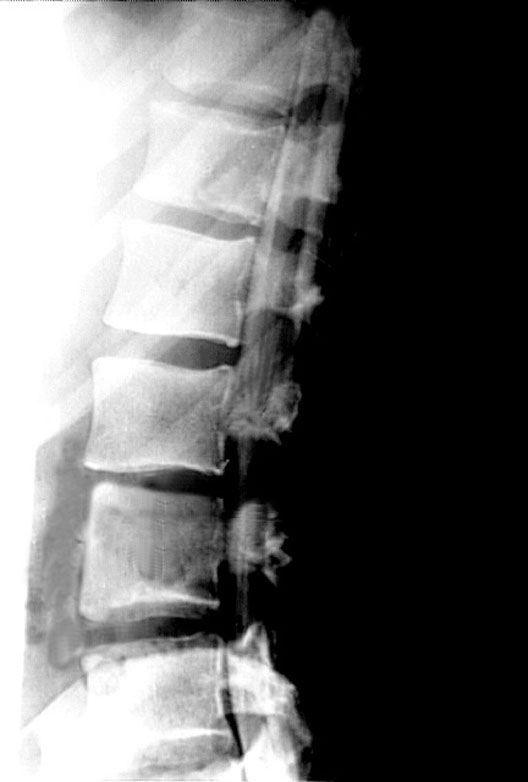

Lumbar Myelogram Lateral View

1. Spinal cord

2. Contrast in subarachnoid space

3. Intervertebral disc

4. Nerve rootlets of cauda equina